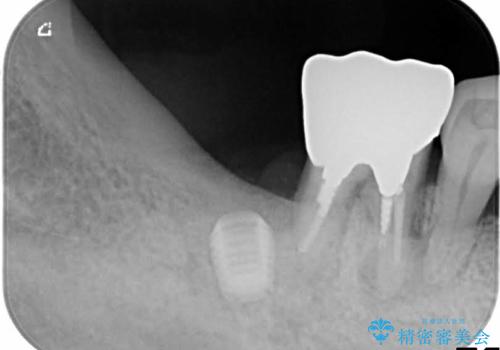

歯周病でぐらぐらになってしまった奥歯を抜歯し、残る骨の高さを鑑みてショートインプラントを選択しました。

インプラントの種類:Bicon

かぶせ物の種類:Bellezza